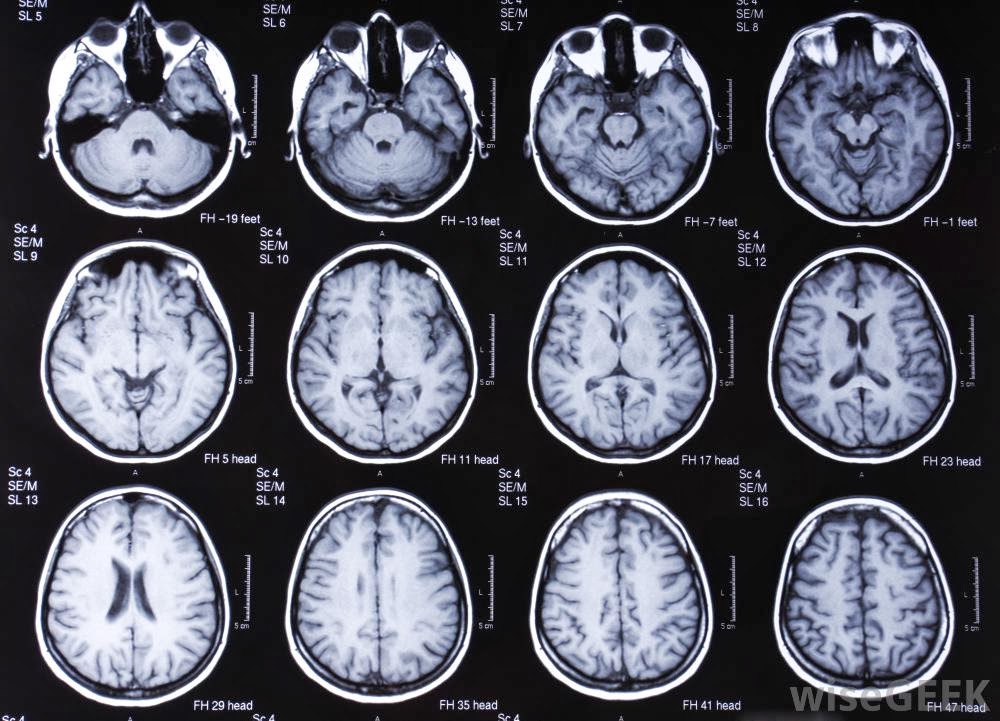

What is magnetic resonance imaging (MRI)? MRI, creates pictures that can show differences between healthy and unhealthy tissue. Doctors use MRI to examine the brain, spine, joints Items that need to be removed by patients before entering the MRI scan-ner room include:-Purse, wallet ... Document Viewer

A PATIENT’S GUIDE TO Magnetic Resonance Imaging (MRI) Scheduling Phone: and unhealthy tissue therefore is used to diagnose many conditions. Doctors use MRI to examine the brain, spine, joints, abdomen, pelvic ... Access Doc

Abstract-Tumor is unwanted growth of unhealthy cell which increase intracranial Preprocessing, Segmentation, feature extraction and detection of tumor from MRI scanned brain images. Magnetic Resonance Imaging (MRI Magnetic Resonance Imaging (MRI) scan Computed Axial ... Fetch This Document

Abstract— Tumor is unwanted growth of unhealthy cell which increase intracranial pressure within skull. (MRI) scan Computed Axial Tomography (CAT) scan Positron Emission Tomography (PET) Obtain MRI brain scanned image of patients and respective medical diagnosis from medical ... Get Content Here

Region growing for MRI brain tumor volume analysis R. B. Dubey1, M. Hanmandlu2, Imaging of the tumors can be done by CT scan, Ultrasound and MRI etc. The MR imaging method is the best due to its higher resolution shows the unhealthy portion clearly. From this image the infected portion ... Fetch Document